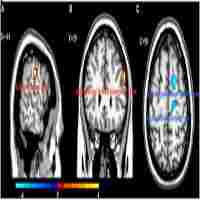

| Abstract | Background Although symptoms of depressive episodes in patients with bipolar depressive episodes (BDE) and major depressive disorder (MDD) are similar, the treatment strategies for these disorders are completely different, suggesting that BDE and MDD have different neurobiological backgrounds. In this study, we examined the relationship between brain function and clinical symptoms, particularly cognitive function, in female individuals with bipolar disorder and MDD experiencing depressive episodes. Methods Regional homogeneity (ReHo) was analyzed in 51 medication-free female patients with BDE, 63 medication-free female patients with MDD, and 45 female healthy controls (HCs). Depressive symptom severity was assessed using the 24-item Hamilton Depression Rating Scale (HAMD-24), and multidimensional cognitive function was evaluated using the MATRICS Consensus Cognition Battery. Partial correlation analysis was used to explore the links between the brain regions and clinical characteristics. A support vector machine (SVM) was used to assess the classification accuracy. Results Compared with HCs, patients with BDE and MDD had decreased ReHo in the left lobule VI of the cerebellum and increased ReHo in the left precuneus. Patients with BDE also had reduced ReHo in the left lobules IV–V of the cerebellum and increased ReHo in the right putamen, unlike patients with MDD who had no significant differences in these regions. Patients with BDE exhibited more severe cognitive deficits in processing speed, attention, word learning, and overall cognitive function than those with MDD. In patients with BDE, a significant negative correlation was found between the right putamen and HAMD-24 scores. However, no significant association was observed between abnormal ReHo levels and cognitive function. The SVM effectively differentiated between patients with BDE, MDD, and HCs. Conclusion Cognitive impairment was more severe in female patients with BDE than in those with MDD. Changes in the ReHo values of the right putamen and left lobules IV–V may serve as unique neuroimaging markers for BDE. Alterations in the ReHo values of the left precuneus and left lobule VI could serve as common pathophysiological mechanisms for BDE and MDD in women and indicate depressive states. |